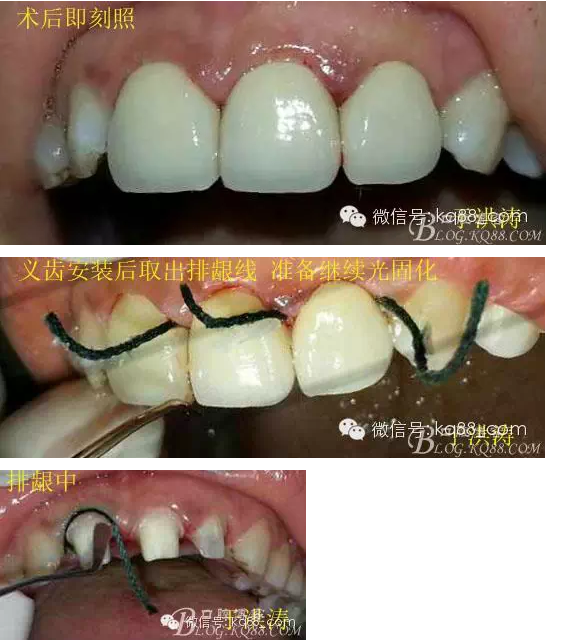

治療過程:義齒制作完成。去除臨時冠及粘結(jié)物。義齒試戴調(diào)整完全就位,無懸突,無縫隙。清洗義齒,氫氟酸處理義齒50秒(加強醫(yī)患防護),沖洗吹干,偶聯(lián)劑處理備用。基牙37%酸處理15秒,沖洗吹干,隔濕,排齦,涂第五代粘結(jié)劑。小蜜蜂雙固化樹脂水門汀激活攪拌注入義齒中,按順序就位,加壓力,牙線去除牙縫隙多余樹脂,涂阻氧劑,基牙唇腭側(cè)各光照固化3秒之后去除多余水門汀取出排齦線,繼續(xù)光照固化牙齒每個面20秒。精細查找去除多余水門汀。

各步驟操作見下圖

于洪濤 2015.04.07